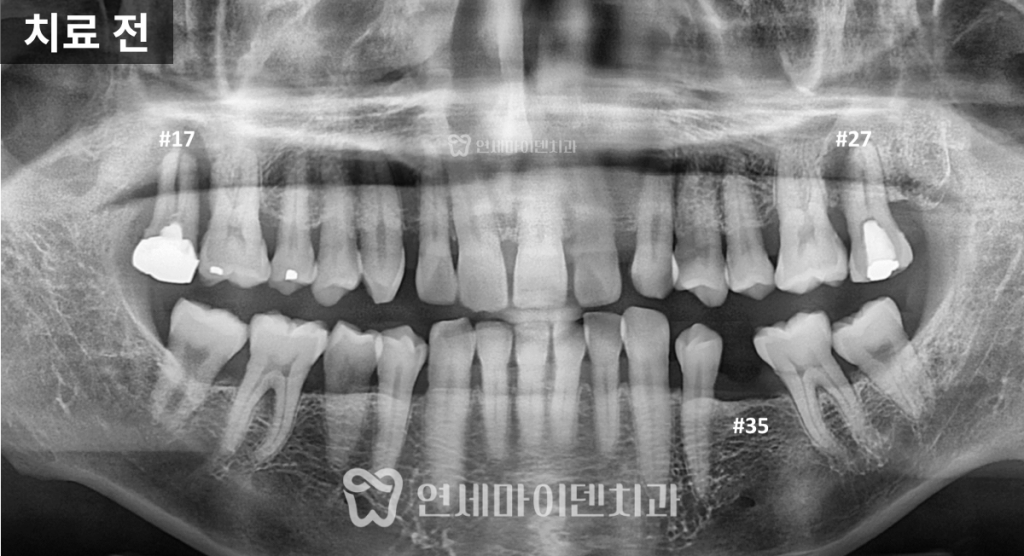

빠른 판단이 필요합니다.치료 전 상태: 뼈가 거의 없는 상황

이번 환자분은

오른쪽 위 어금니는 심하게 흔들리는 상태였고

아래 왼쪽 어금니는 발치 후 오래 방치되었습니다.

CT를 확인해보니

뼈가 거의 남아 있지 않았고,

손으로도 발치가 가능할 정도였습니다.이 상태를 오래 두면